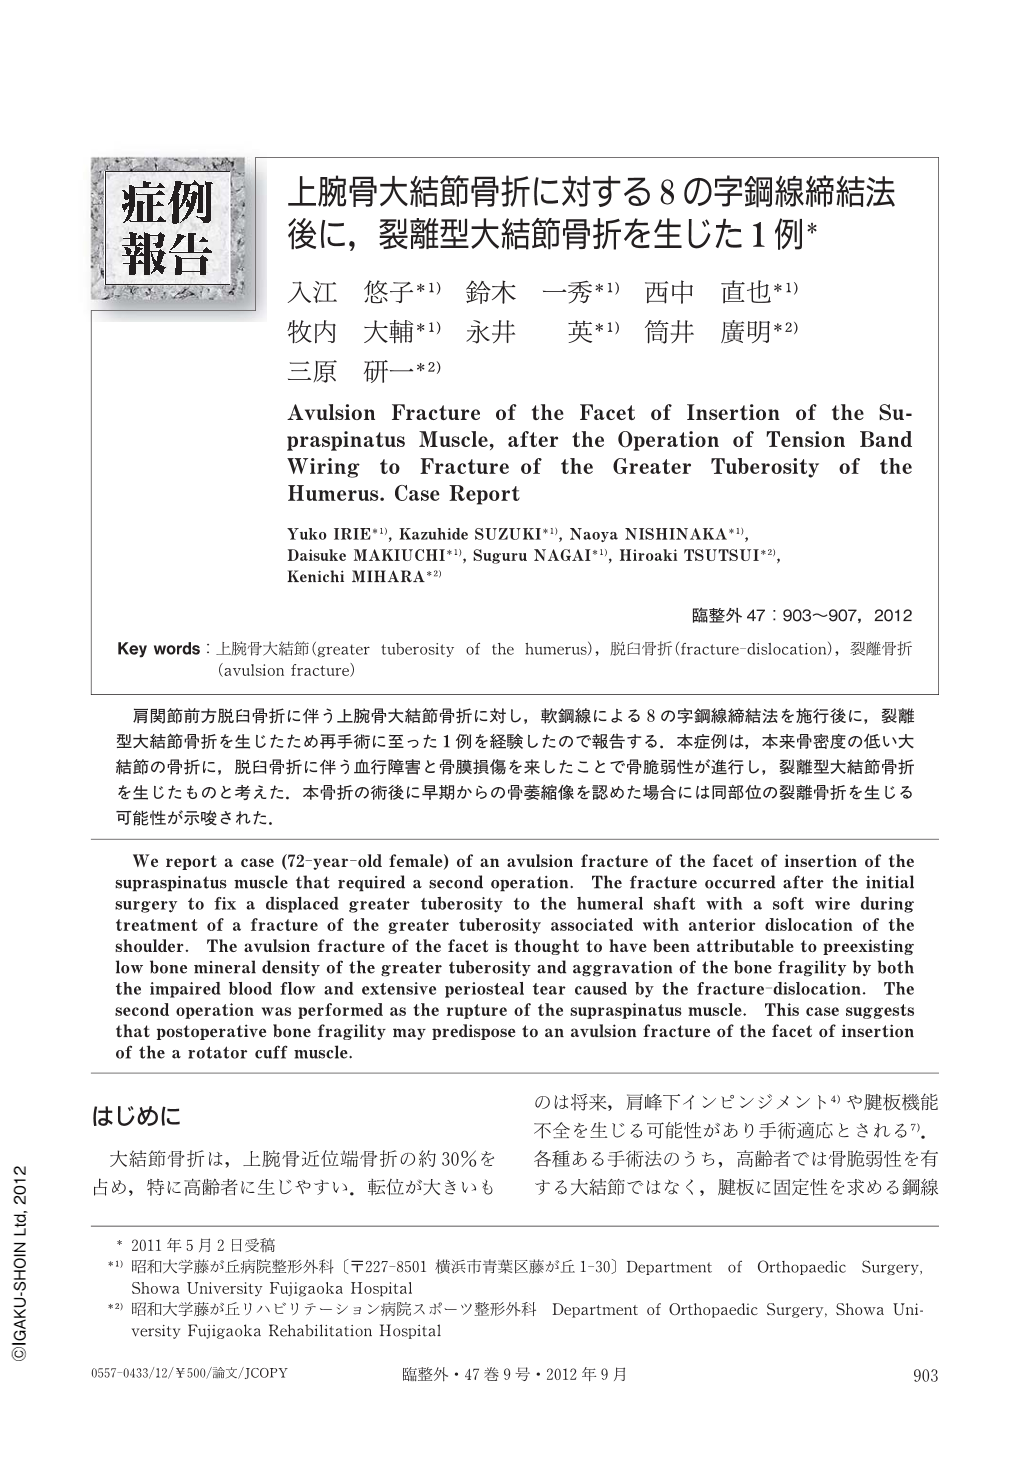

上腕骨大結節骨折に対する8の字鋼線締結法後に 裂離型大結節骨折を生じた1例 臨床整形外科 47巻9号 医書 Jp